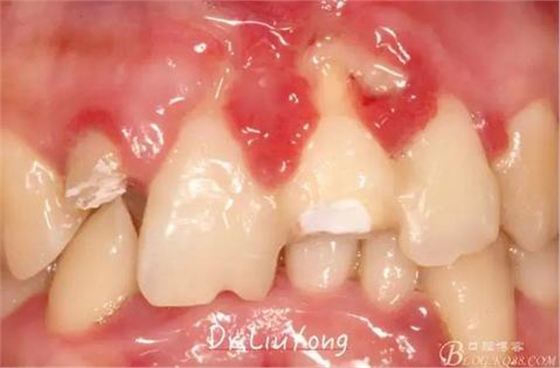

在松動牙固定的同時,嘗試保留B1唇側折裂牙槽骨塊,拆除縫線后,局部沖洗,牙周塞治劑覆蓋并固定游離骨塊。囑患者加強口腔衛(wèi)生,氯己定漱口液含漱,兩周后復查。兩周后拆除塞治劑,骨塊仍為游離活動狀態(tài),去除游離骨塊,局部沖洗上藥。

骨塊固定兩周后復查,如上圖